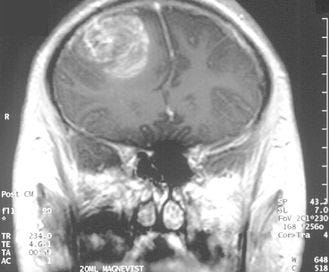

Pandemic of the Glioblastomas?